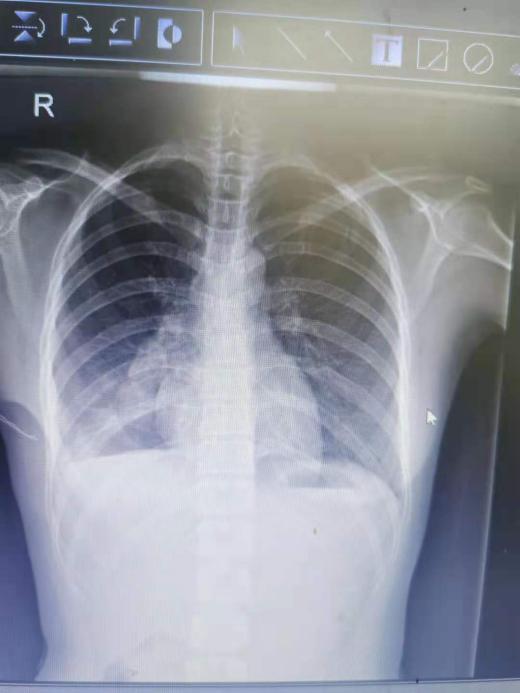

23岁的患者小芳在体检时发现肺部有磨玻璃样结节到我院就诊,经诊断性抗感染治疗后磨玻璃结节病灶未吸收,需手术治疗进一步确诊。而此时小芳犹豫了,一方面她担心不尽快手术会耽误疾病的诊治;另一方面,她觉得自己还那么年轻就要接受开胸手术,在她的印象中,胸腔肺部手术风险巨大,且不说住院时间大大延长,还要忍受手术后在身上插满各种管子,术后久久不能醒来,还有手术后剧烈的疼痛……一想到这些,她的内心充满了恐惧。在了解到小芳的顾虑后,主持手术的梁勋斯副主任医生立即将情况跟科主任张爱平汇报。